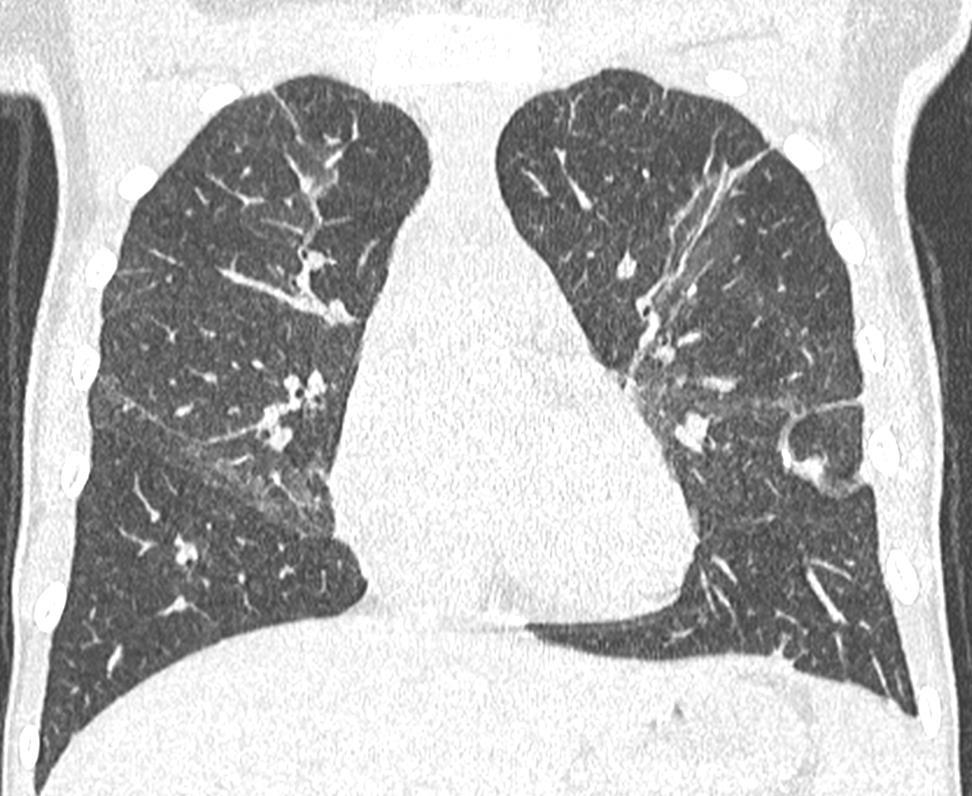

ADENOVIRUS

Bronchiolar and alveolar damage

Chickenpox

47

Imaging of Covid 19 infection in children